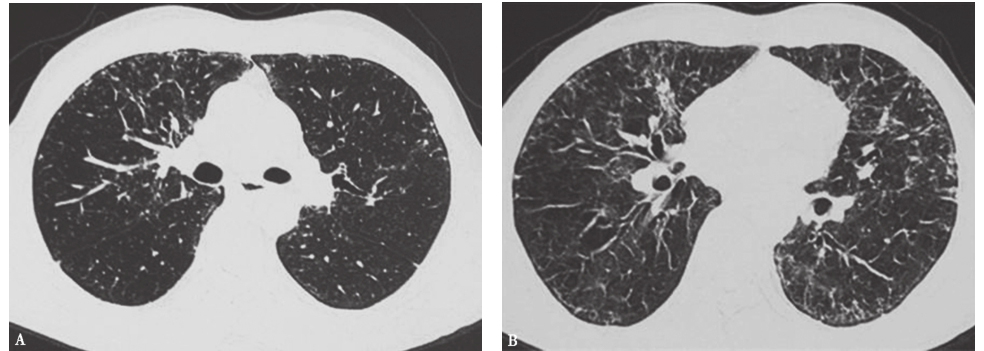

外院胸部CT示两肺散在磨玻璃影、弥漫性小结节影(图1),局部可见牵拉性支气管扩张。

图1外院胸部CT表现

两肺散在磨玻璃影及小结节影(图13),局部网状影,较入院前(图1)明显吸收、好转。

图13入院后胸部HRCT表现

患者入院后所做系列检查显示:①自身抗体均阴性,结合临床表现,基本可排除风湿免疫病;②常规病原学检查均阴性;③胸部HRCT可见两肺小结节影、磨玻璃影,较外院CT明显吸收、好转,证明外院激素治疗有效。此外,患者在未接受抗肿瘤治疗的情况下小结节影吸收、好转,与肺转移癌不符(由于癌细胞不断增殖,粟粒状癌灶可在短时间内渐进性增大)。